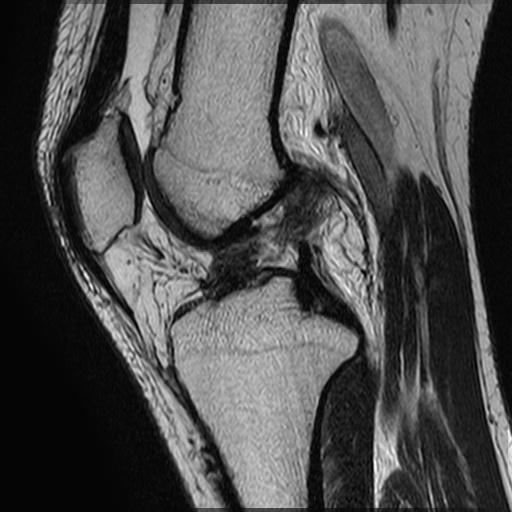

実際に来院される患者さんを想定した内容で進め整形外科領域では多く来院される患者さんの状態合わせた内容としています。

症状や病態の研修の他にも診療報酬や電子カルテの操作方法、内科疾患や患者さんのリスク管理についても研修を行っております。